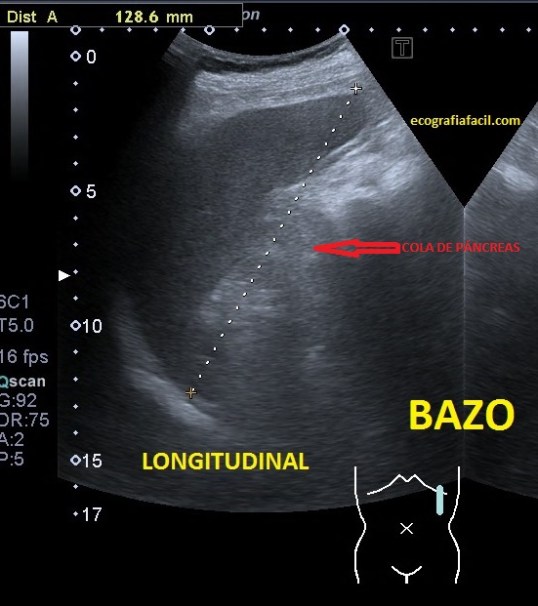

52. Protocolo de Abdomen. El Bazo.

Después del Riñón derecho, nos vamos hacia el lado izquierdo, concretamente al Hipocondrio Izquierdo, allí encontramos el Bazo.

Es un órgano intraperitoneal.

Está en continuidad con el diafragma. Contacta con el riñón izdo. Inferiormente y con el estómago y la cola del páncreas medialmente.

Partiremos de la posición en longitudinal en línea axilar media izquierda a la altura de la 9-10 costilla y ahí buscaremos el órgano según anatomías. Hacemos cortes transverso y longitudinal.

Ecográficamente es una estructura voluminosa, hiperecogénica y homogénea que no debe medir en adultos más de 12 cms. Los vasos de la estructura se verán anecoicos.

Para terminar os voy a comentar que estas proyecciones son útiles para estudiar posibles lesiones de la cola de Páncreas y tenemos la experiencia contrastada de hallazgos patológicos en dicha localización desde este acceso no vistos en el acceso por vía normal para el estudio del Páncreas. En estas proyecciones el la cola pancreática se ve ligeramente hiperecogénica junto al borde interno del Bazo, cerca de su hilio. En la siguiente foto te lo marco en Rojo. Esta visualización de la cola pancreática requiere más experiencia y estar habituado a la técnica.

Localización cola pancreática.